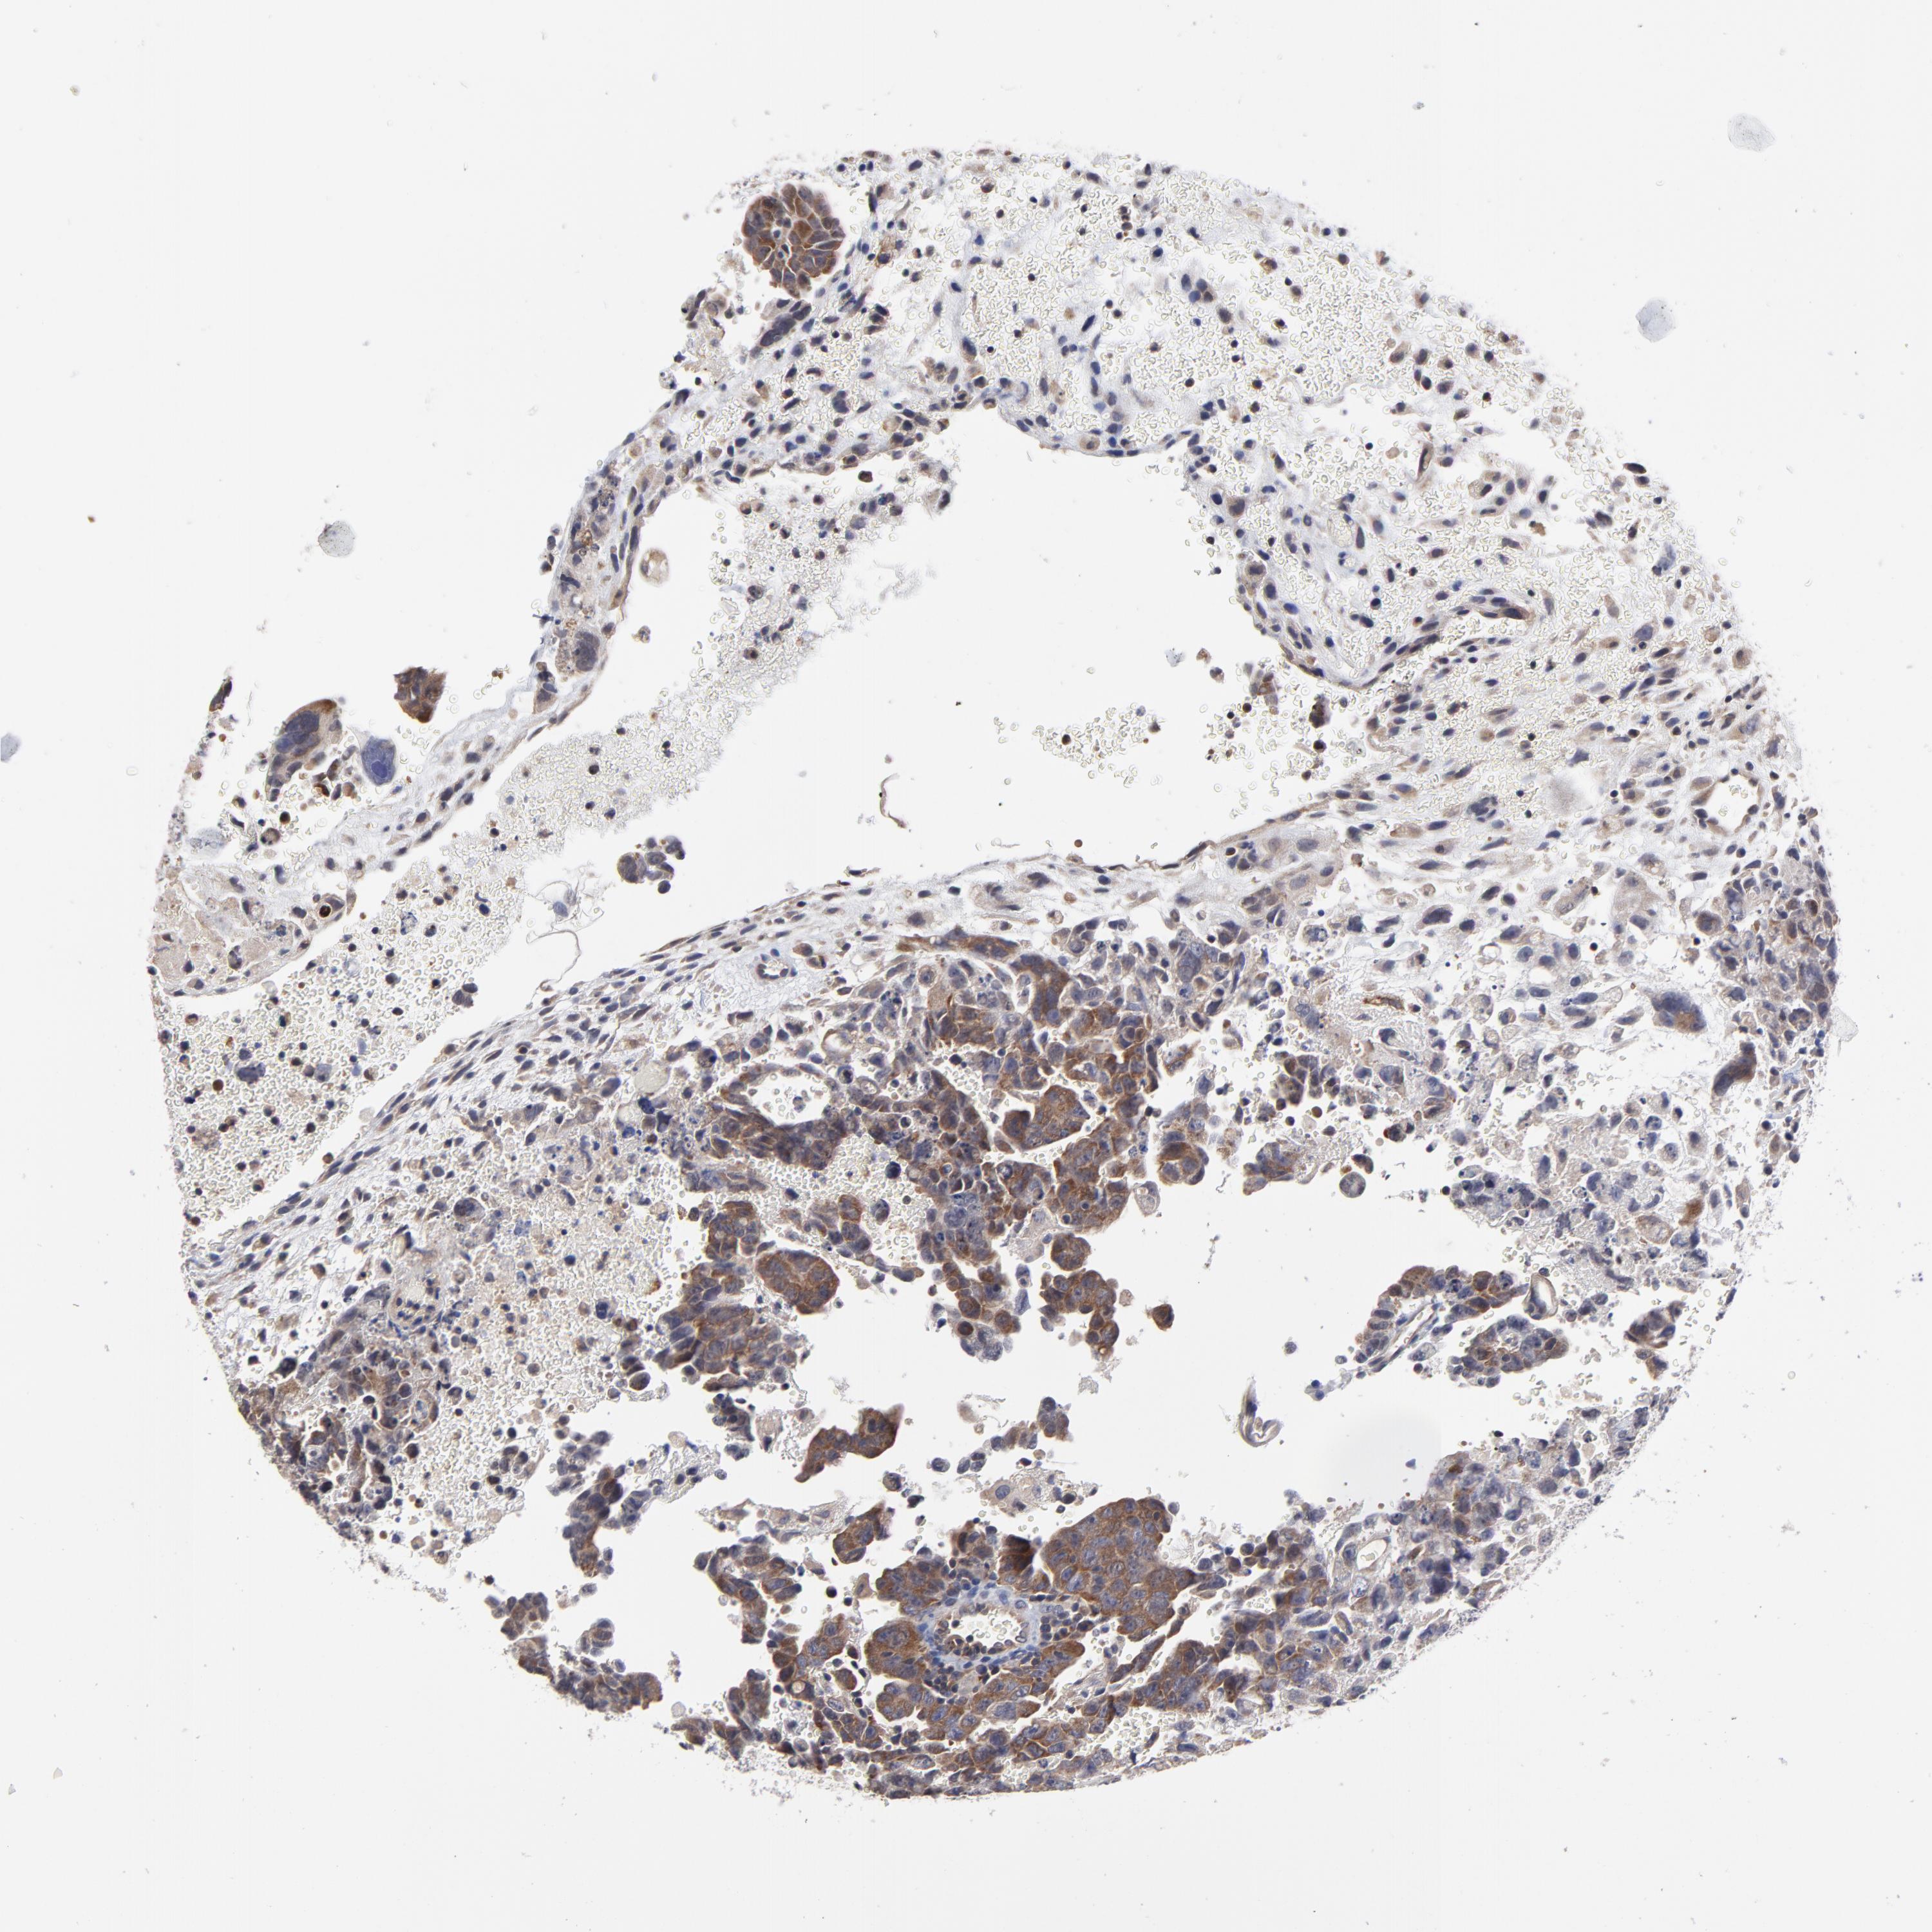

TESTIS CANCER - Protein expressioni

A mouse-over function shows sample information and annotation data. Click on an image to view it in a full screen mode. Samples can be filtered based on level of antibody staining by selecting one or several of the following categories: high, medium, low and not detected. The assay and annotation is described here.

Note that samples used for immunohistochemistry by the Human Protein Atlas do not correspond to samples in the TCGA dataset.

Antibody stainingi

Antibody staining in the annotated cell types in the current human tissue is reported as not detected, low, medium, or high, based on conventional immunohistochemistry profiling in selected tissues. This score is based on the combination of the staining intensity and fraction of stained cells.

Each image is clickable and will lead to virtual microscopy that enables deeper exploration of all samples and also displays staining intensity scores, fraction scores and subcellular localization as well as patient and tissue information for each sample.

Antibody HPA003319

Staining

High

Medium

Low

Not detected

Intensity

Strong

Moderate

Weak

Negative

Quantity

>75%

75%-25%

<25%

None

Location

Nuclear

Cytoplasmic/membranous

Cytoplasmic/membranous,nuclear

Carcinoma, Embryonal, NOS

Seminoma, NOS